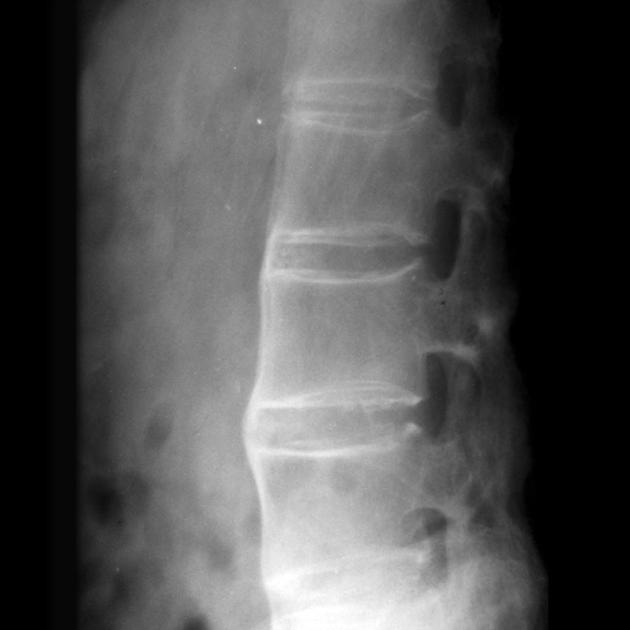

随着疾病的进展,脊柱的活动度会逐渐受到限制

这种限制不是一夜之间发生的,而是一个渐进的过程,就像温水煮青蛙一样,让人不易察觉